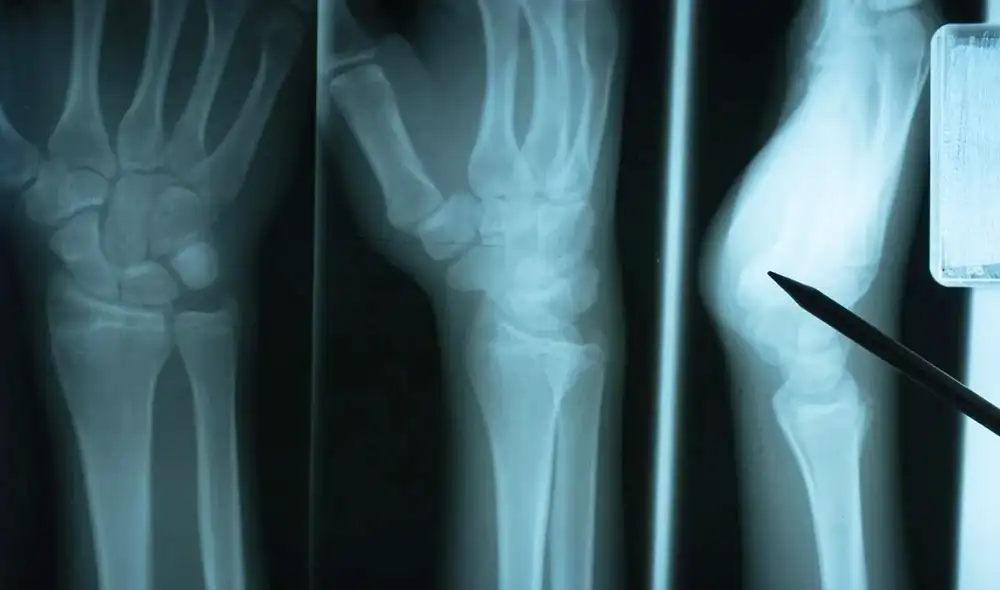

Estudio científico descubre proteína clave para la reparación de huesos después de sufrir una fractura

Un estudio titulado “APEX1, a transcriptional hub for endochondral ossification and fracture repair”, publicado en la revista científica Bone Research, identificó un mecanismo celular clave que influye directamente en la consolidación de fracturas y en el riesgo de pseudoartrosis, una complicación que impide la correcta unión de los huesos. La investigación, centrada en la proteína APEX1 y su papel en la reparación ósea, revela que el equilibrio de ciertas señales químicas dentro de las células es determinante para una recuperación eficaz.

El estudio identificó a la proteína como un regulador central en la respuesta celular durante la reparación de fracturas. Esta molécula participa en la detección y corrección de daños en el ADN, además de intervenir en la señalización intracelular vinculada al estrés oxidativo. Su actividad permite que las células óseas respondan de manera adecuada a las condiciones generadas tras una lesión.

Los investigadores observaron que una regulación deficiente altera la comunicación molecular necesaria para activar los mecanismos de reconstrucción. Esta disfunción puede retrasar la formación de nuevo tejido y aumentar la probabilidad de pseudoartrosis, una condición que afecta la estabilidad estructural del hueso y prolonga el tiempo de recuperación.